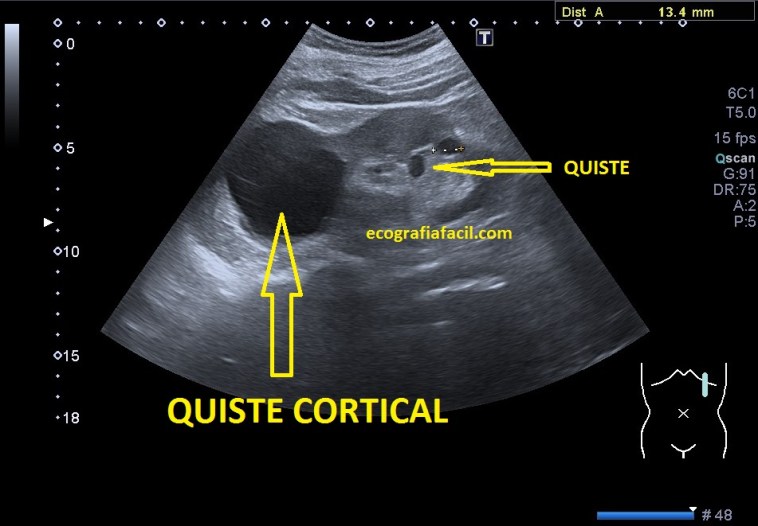

Quistes:

Los quistes se clasifican en:

1. Corticales.

2. Parapiélicos.

3. Sinusales.

Los quistes simples ecograficamente son anecoicos, presentan refuerzo posterior y su forma es redondeada u ovalada.

Los quistes complejos, contienen ecos en su interior, Presentan septos y calcificaciones.

Diferentes tipos de presentaciones quísticas.